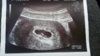

Nasze testy, brzuszki, usg, wyniki :)

Mój test 5 dni po braku planowanej miesiączki [emoji6]